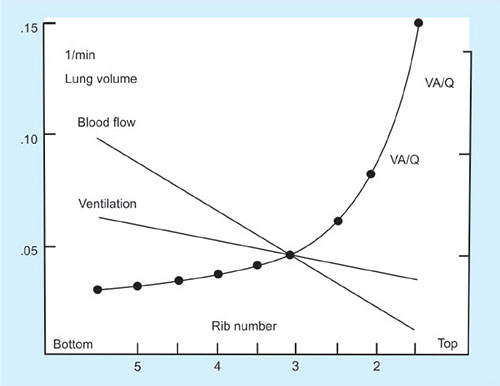

Distribution of Ventilation and Perfusion

The efficiency with which oxygen and carbon dioxide exchange at the alveolar-capillary level highly depends on the matching of capillary perfusion and alveolar ventilation. At this level, the combination of lung and the circulatory system must be well-matched.

Ventilation-Perfusion Relationships

The majority of blood flow is distributed to the gravity-dependent part of the lung. During a spontaneous breath, the largest portion of the tidal volume also reaches the gravity-dependent part of the lung.40

Thus, the nondependent area of the lung receives a lower proportion of both ventilation and perfusion, and dependent lung receives greater proportions of ventilation and perfusion. But, ventilation and perfusion are not matched perfectly, and various V/Q ratios result throughout the lung (Fig. 32).

Any discrepancy between ventilation and blood flow in the lung will result in V/Q mismatch and potentially dangerous irregularities in gas exchange.

If flow of blood to the lung units is to match that of ventilation to the same unit then the ratio of ventilation to perfusion should be in a ratio of 1:1.

If the lung is being underventilated but perfused as normal then we say that the V/Q ratio is <1 (Fig. 33).

If the lung is under perfused then the V/Q is >1 (Fig. 33).

Even in a normal lung the V/Q ratio is not uniformly 1 throughout the lung as perfusion and ventilation both have favored parts of the lung. Differences between the apices and bases of the lungs.

At the apices there is less ventilation than the bases as alveoli are already very stretched however there is proportionally less perfusion therefore the overall V/Q ratio is higher compared to the base of the lung.

Blood flow is directly affected by gravity and naturally has a tendency to flow to the bases of the lungs thus V/Q ratios toward the lower segments of the lung are usually greater than 1. The vertical change in V/Q ratios in the lung is because although both ventilation and perfusion increase from top to bottom of the lung, perfusion increases much quicker than ventilation.41

Thus the V/Q ratio at the top of the lung is 3.3 whereas at the bases it is around 0.6.

Ideal V/Q ratio = 1; believed to occur at approximately the level of the third rib.

Above this level, ventilation occurs slightly in excess of perfusion, whereas below the third rib the V/Q ratio becomes less than 1.

V/Q = 0 in shunt

V/Q = infinity in dead space.

Hypoxic pulmonary vasoconstriction and bronchoconstriction allow the lungs to maintain optimal V/Q matching.